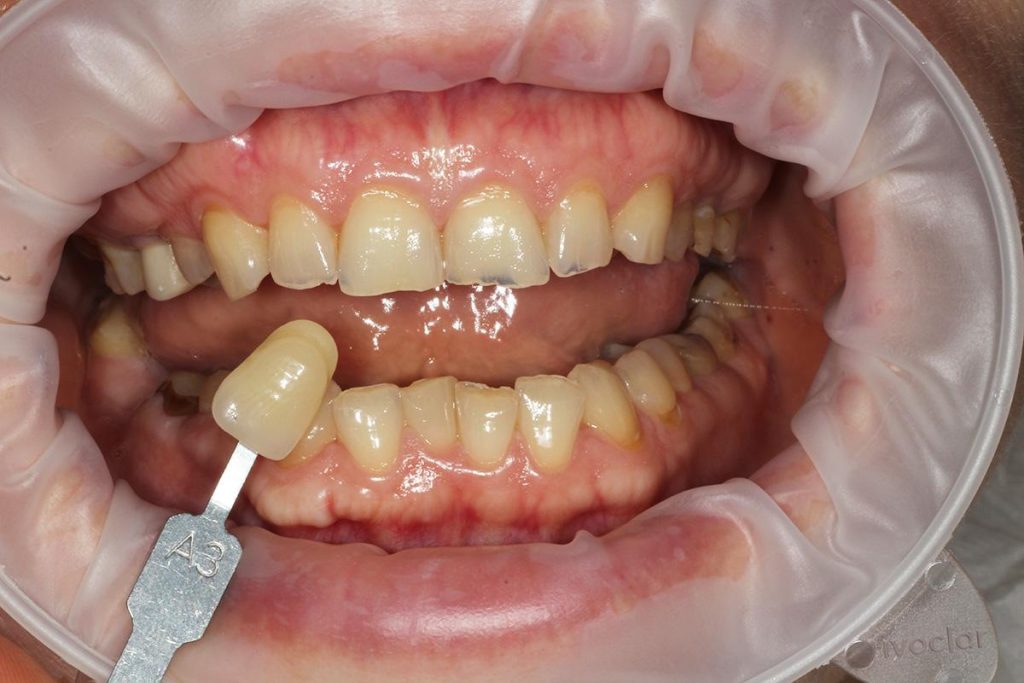

Pod kierownictwem lek. stom. Michała Badowskiego po wnikliwej analizie została przeprowadzona korekta dziąseł i pozbycie się nieestetycznych koron na podbudowie metalowej, eliminując tym samym nawracające stany zapalne dziąseł.

Następnie została wykonana wizualizacja nowego uśmiechu, idealnie dopasowana do twarzy Pacjentki. Po jej akceptacji, przygotowaliśmy komplet koron i licówek pełnoceramicznych na górne i dolne zęby.

Całe leczenie trwało zaledwie 3 miesiące!

Dzięki współpracy lek. stom. Michała Badowskiego i techn. dent. Joanny Gancarz z laboratorium Dentalscan Pacjentka zachwyca pięknym uśmiechem!